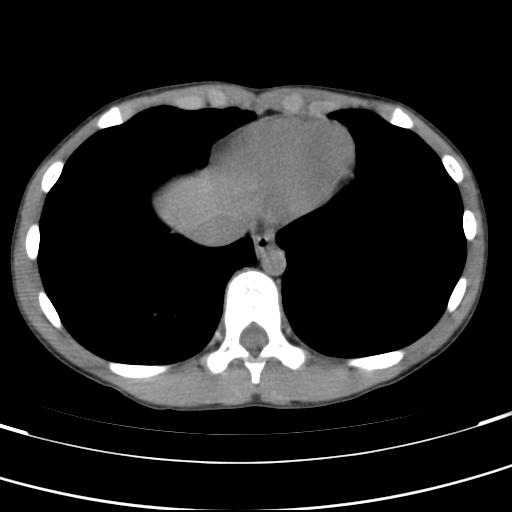

标题: PED3157:左肾缺如,请教脾脏的改变?、、

男孩,9岁。胃部不适。

脾脏位于左侧,但数个脾脏呈分离状态,左肾缺如,右肾代偿肥大。考虑多脾综合征。